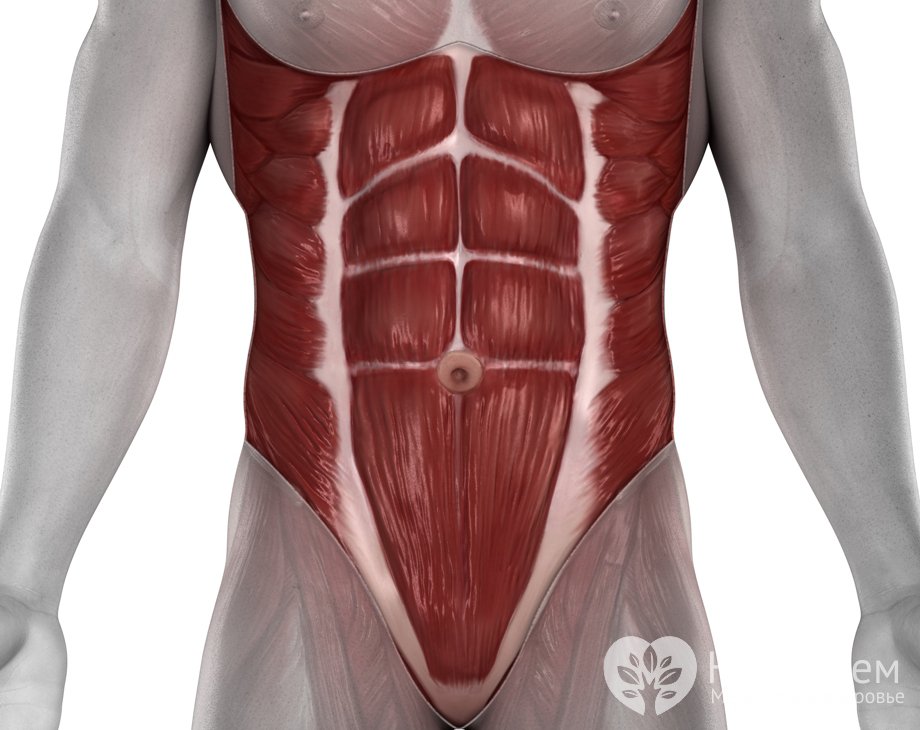

Мышцы живота – группа мышц, расположенная в брюшной полости и обеспечивающая защиту жизненно важных органов, расположенных в ...

Читать далее